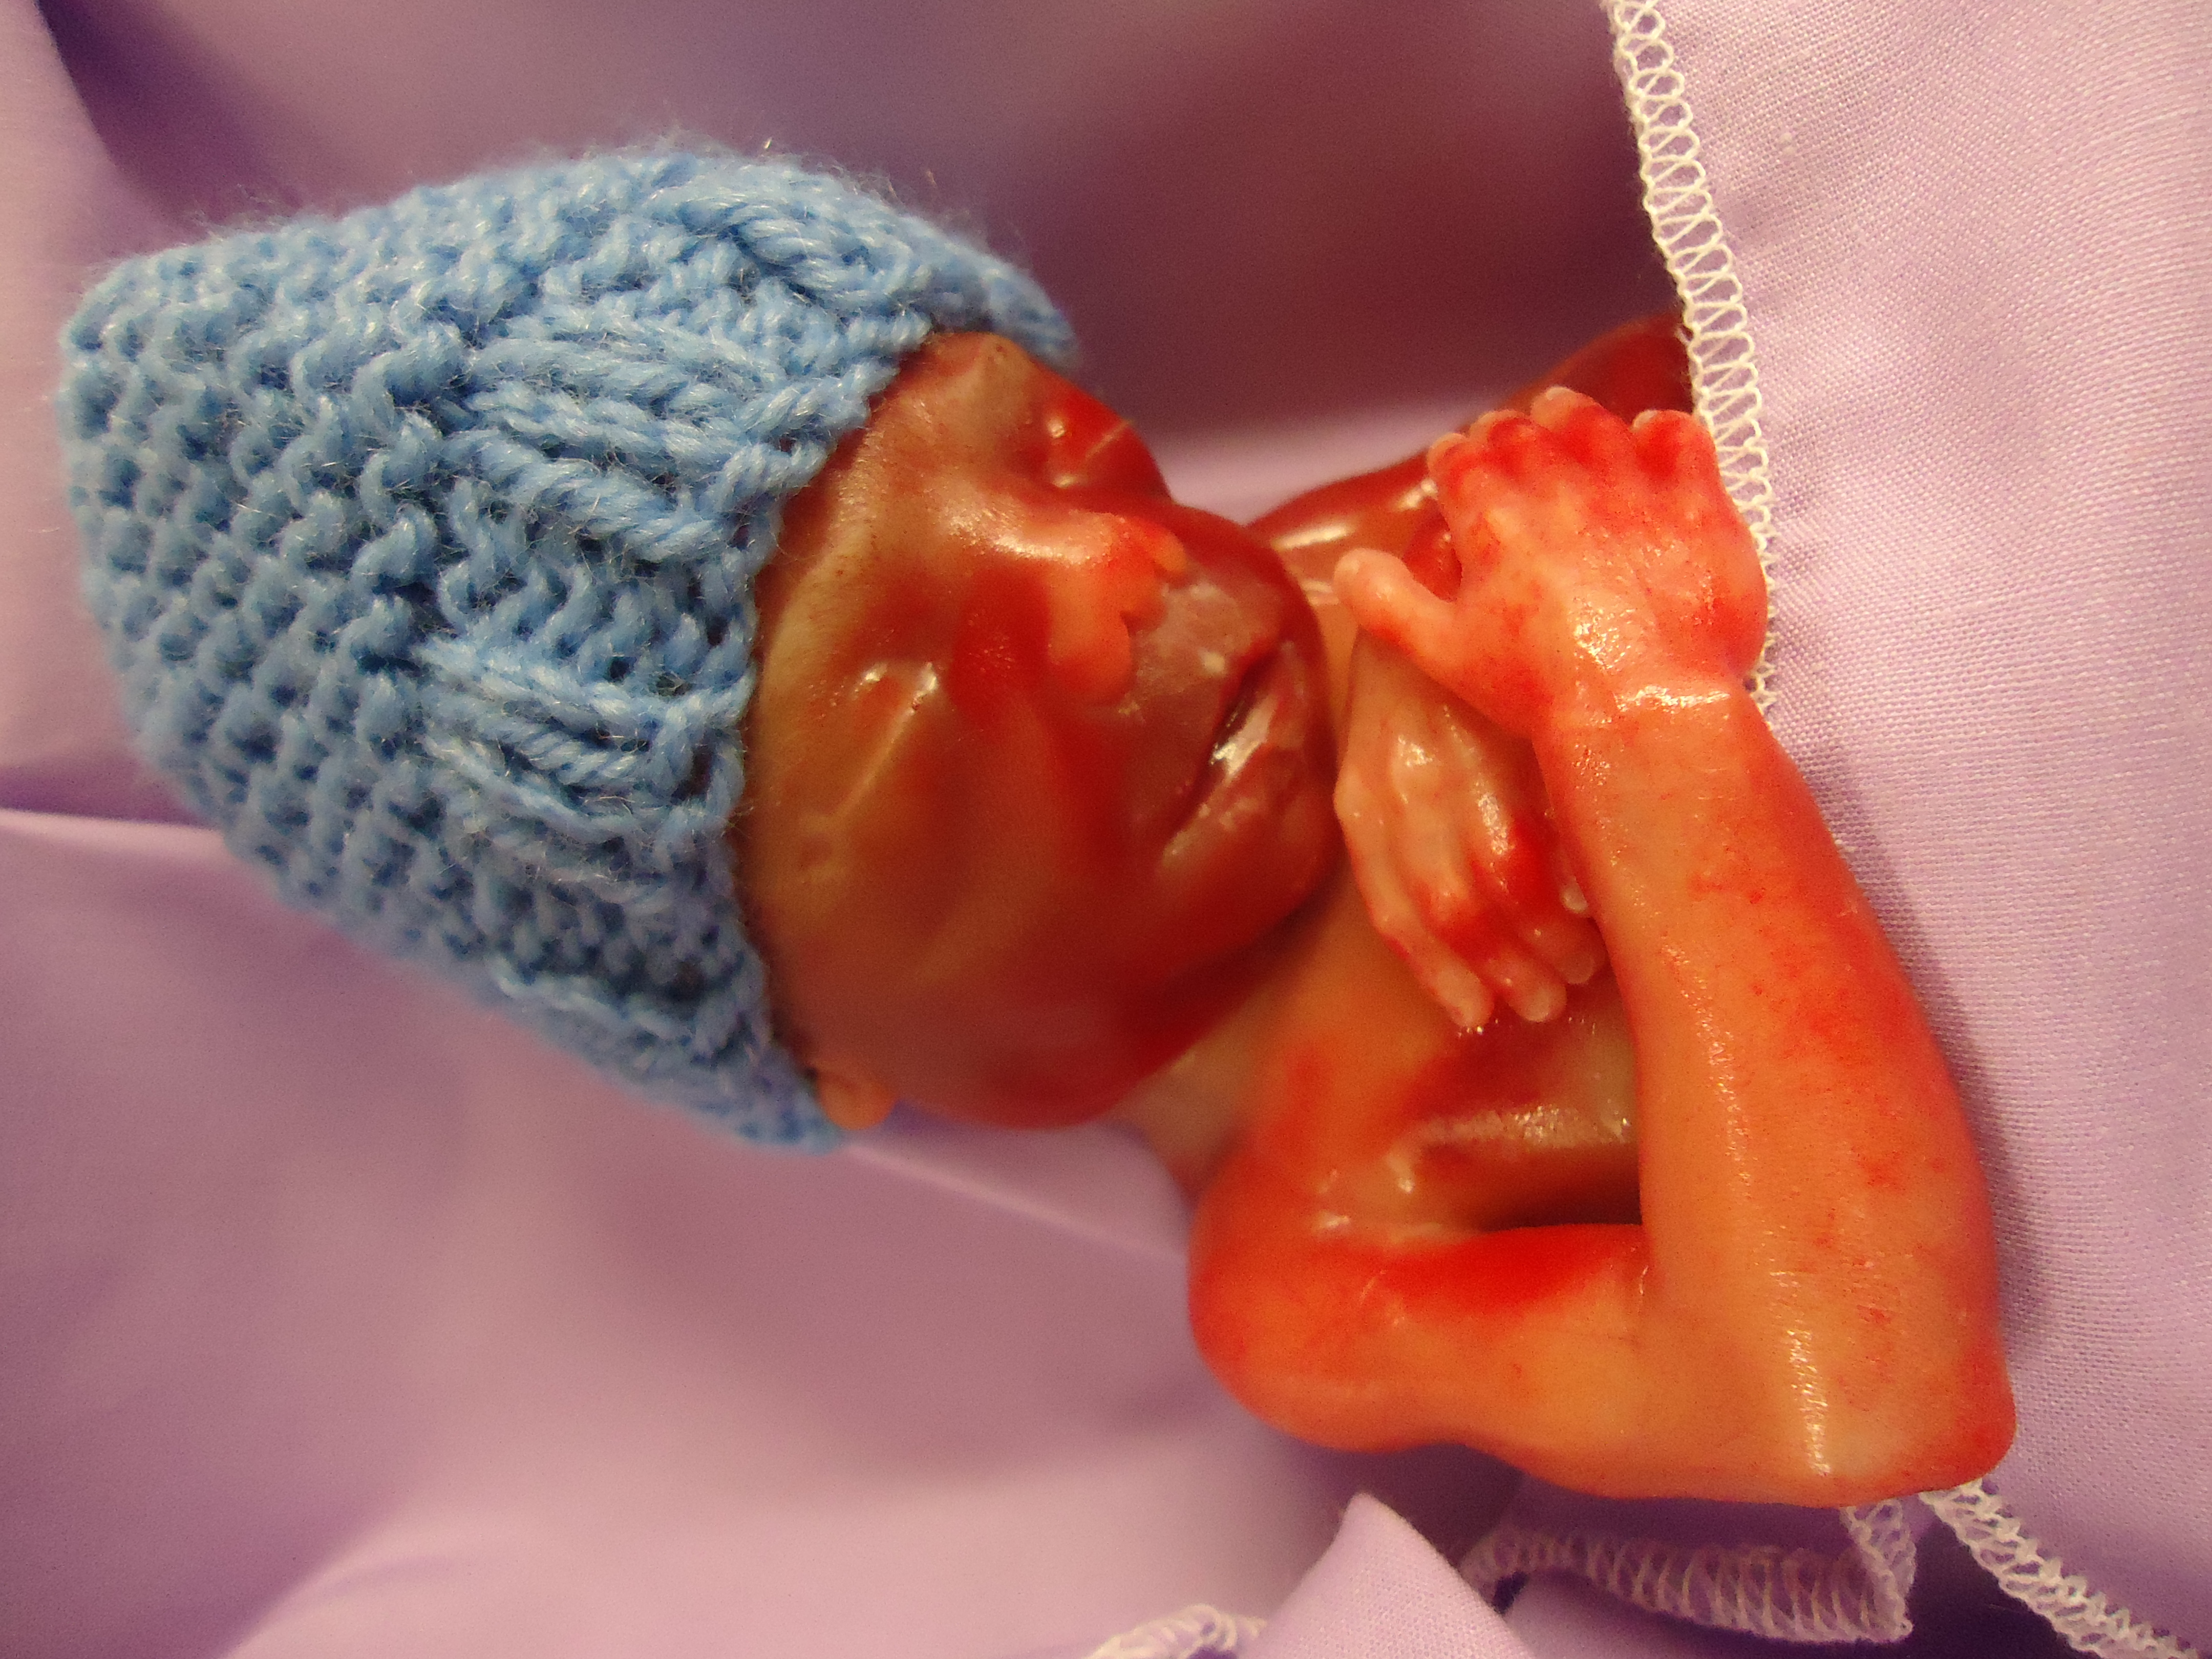

The pregnancy was going along very smoothly with a few little bumps and minor checks at the ER. We were always reassured our little baby was fine. We were not going to find out gender as we wanted to be surprised. On July 4 I went to the E.R. as I was bleeding. They could not find the cause behind it and our sweet baby looked just fine on the ultrasound. I was sent home. On July 5th the bleeding got worse and I started having what I now know our contrations. I had sent my husband to work because I had a brief reprieve of feeling better, but then suddenly my water broke. I called my husband home and we rushed to the hospital where I quickly learned we would be losing our baby. July 5, 2014 at 19 Weeks 5 days gestation, I delivered our sweet little firecracker, our son Gavin Karl Dick in the E.R. He was too little to survive on his own outside the womb and they won’t do life saving measures until 20 Weeks and beyond. He was perfect in everyway. We found out that I had a placental abruption, where the placenta decided to pull away from the uterine wall. We were devastated an heartbroken, leaving the hospital with empty arms. It wasn't fair as we had waited for him for seven years. No parent should ever have to say goodbye to their baby or face this devastating tragedy. This is by far the toughest situation in our lives we have ever encountered, saying hello and goodbye to our son in the same day. There is not a day that goes by where we don’t think about him and miss him.